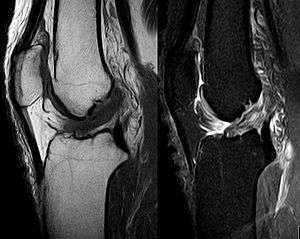

Anterior cruciate ligament tear seen on MRI. T1 left, right PDW.

The pivot-shift test, anterior drawer test, and Lachman test are used during the clinical examination of suspected ACL injury. The Lachman test is recognized by most authorities as the most reliable and sensitive test, and usually superior to the anterior drawer test.[11] The ACL can also be visualized using a magnetic resonance imaging scan (MRI scan).

Though clinical examination in experienced hands can be accurate, the diagnosis is usually confirmed by MRI, which has greatly lessened the need for diagnostic arthroscopy and which has a higher accuracy than clinical examination. It may also permit visualization of other structures which may have been coincidentally involved, such as a meniscus, or collateral ligament, or posterolateral corner of the knee joint.